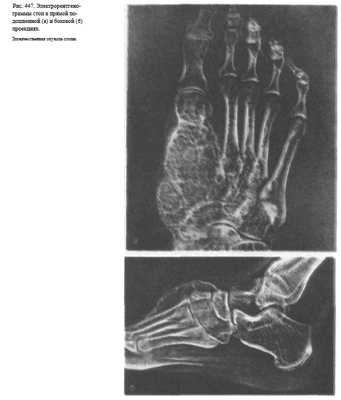

Информативность снимка. На снимке стопы в боковой проекции хорошо видны кости предплюсны: пяточная, таранная, ладьевидная, кубовидная и клиновидная. Кости плюсны проекционно наслаиваются друг на друга. Из всех костей наиболее отчетливо видна V плюсневая кость (рис. 446). На снимках стопы могут быть выявлены различные травматические, воспалительные и опухолевые поражения костей.

Изменения мягких тканей особенно наглядно видны на электро-рентгенограммах (рис. 447, а, б).